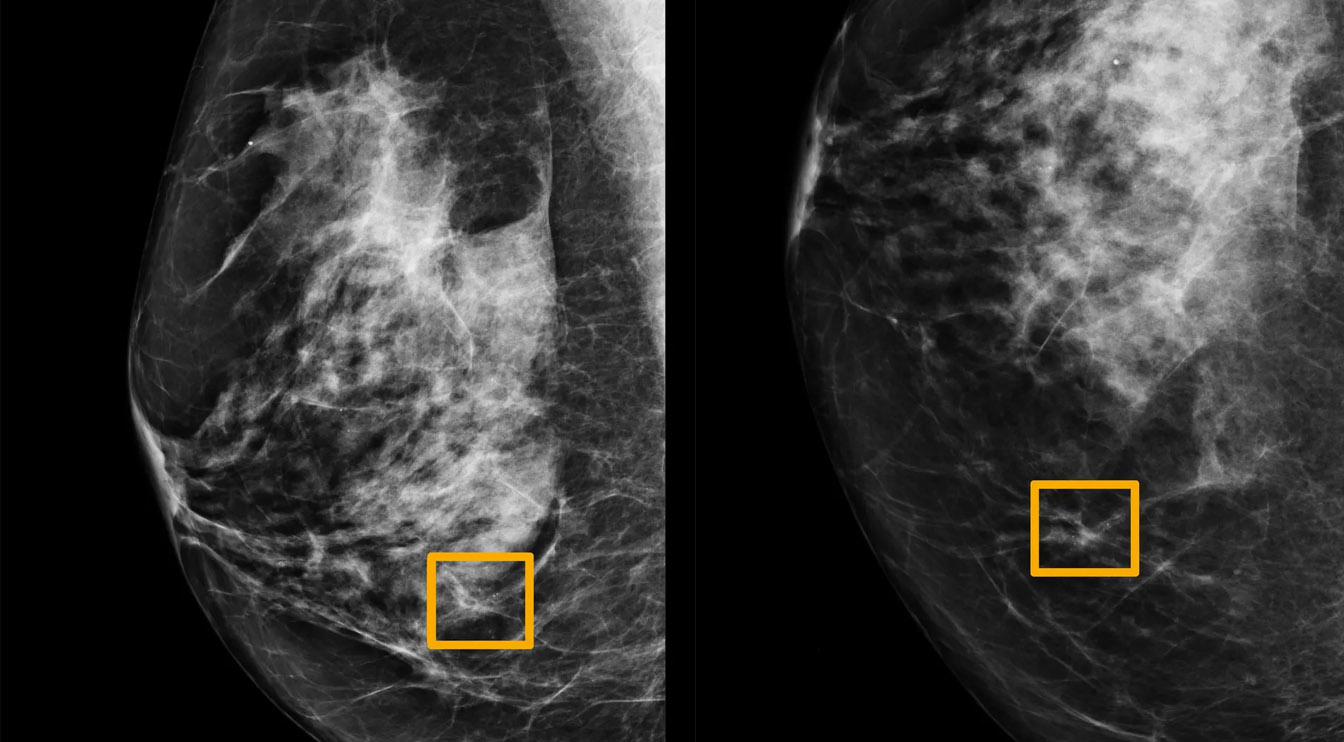

Dalam temuan Google yang berkolaborasi dengan berbagai peneliti kanker ini, AI Google mampu membaca ‘mammogram’ (foto x-ray payudara) dengan persentase keberhasilan yang cukup tinggi.

AI Google mampu menurunkan nilai false negative sampai 9,4 persen, jauh lebih rendah dibanding rata-rata false negative saat ini sebesar 20%. False negative terjadi ketika dokter menyimpulkan seorang pasien tidak terjangkit kanker payudara, padahal ternyata iya.

Tingkat false negative ini relatif tinggi karena “membaca” mammogram bukan perkara mudah, bahkan bagi dokter berpengalaman sekalipun. Contohnya pada payudara yang padat (dense breast), hasil mammogram seringkali tidak mampu menangkap keberadaan tumor.